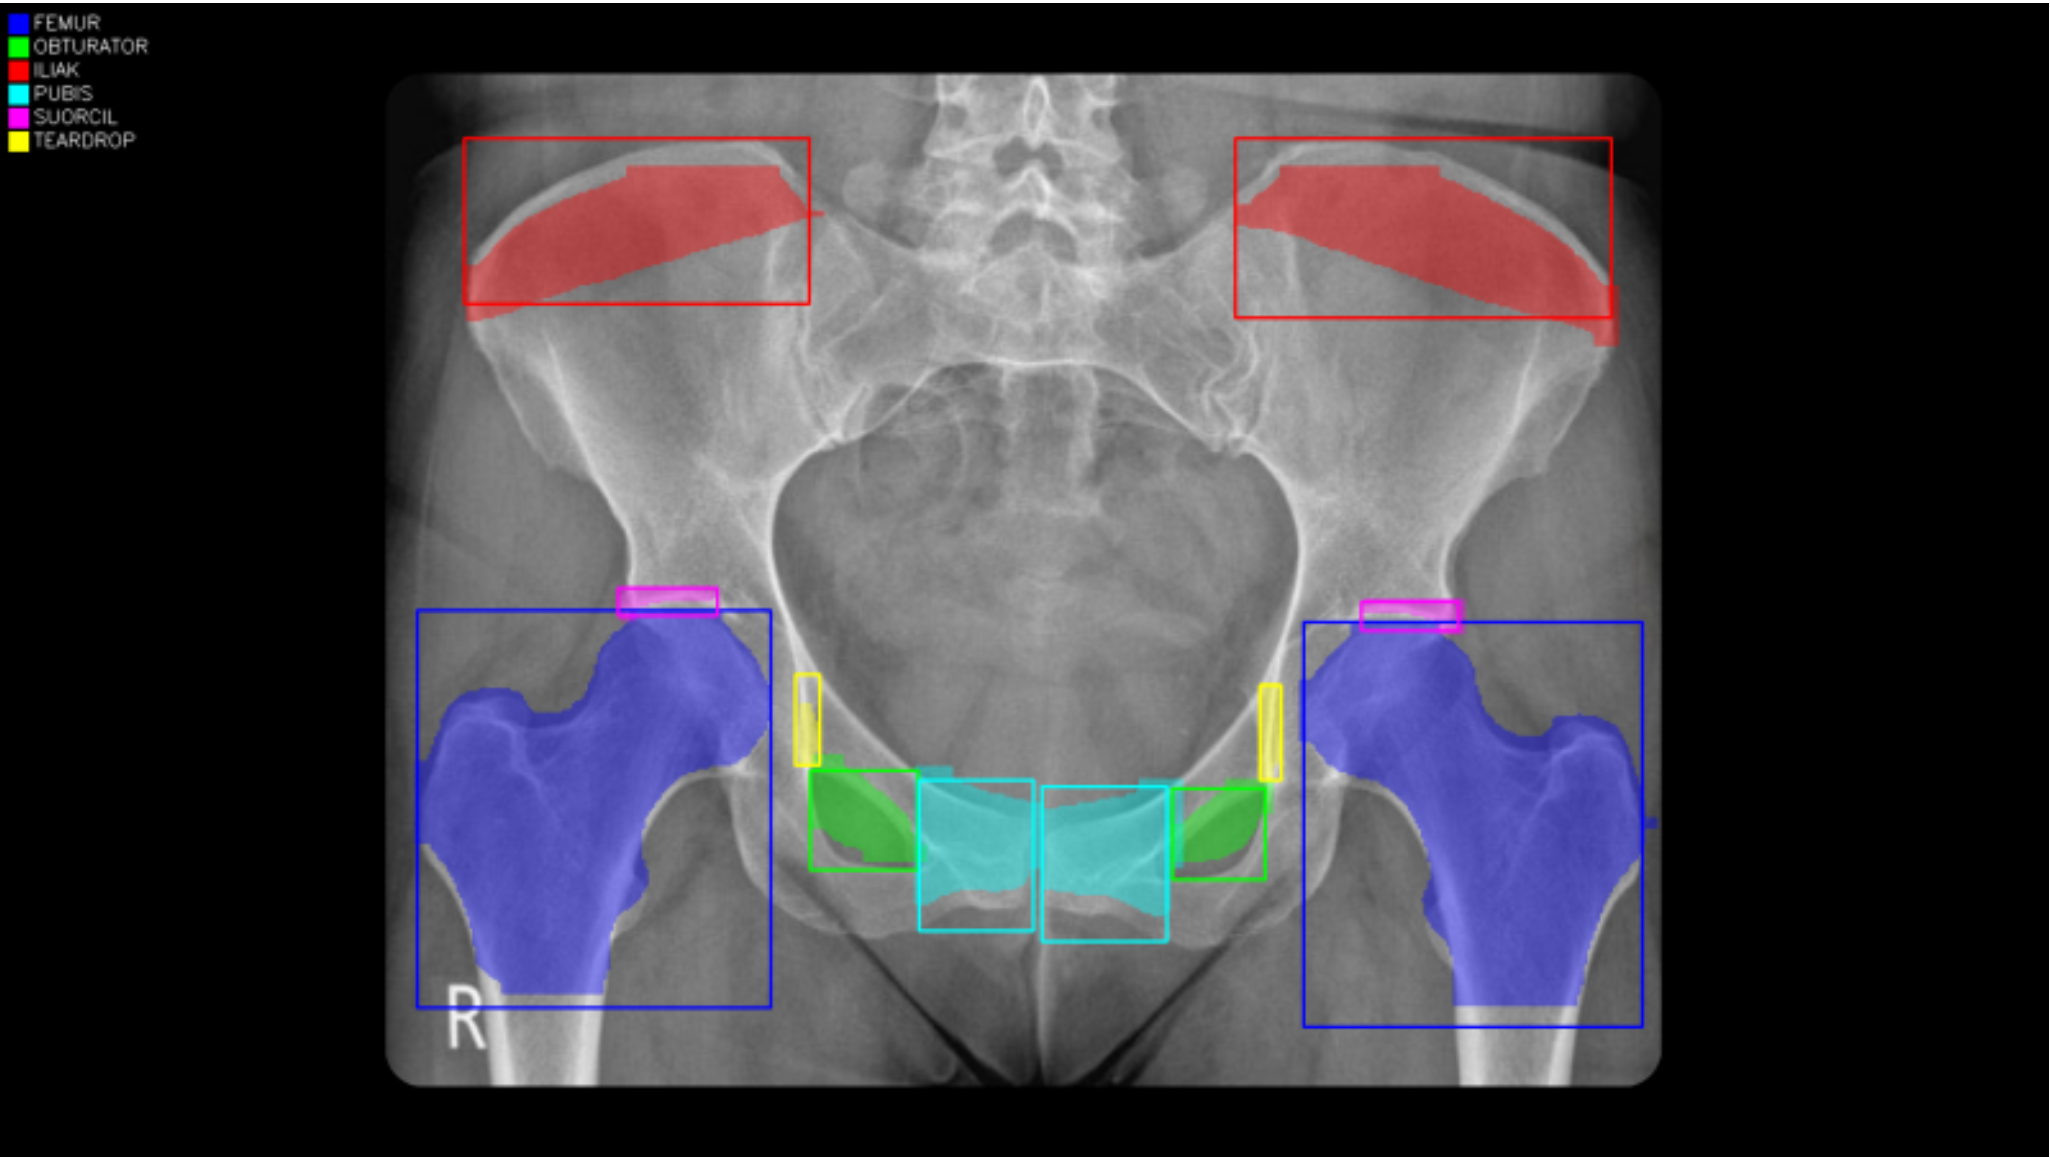

X-ray ve Anatomik Lokasyon Analizi

Cep Doktorum’da kullanılan görüntü analiz modelleri; kemik yapıları ve anatomik bölgeleri otomatik olarak tanımlar.